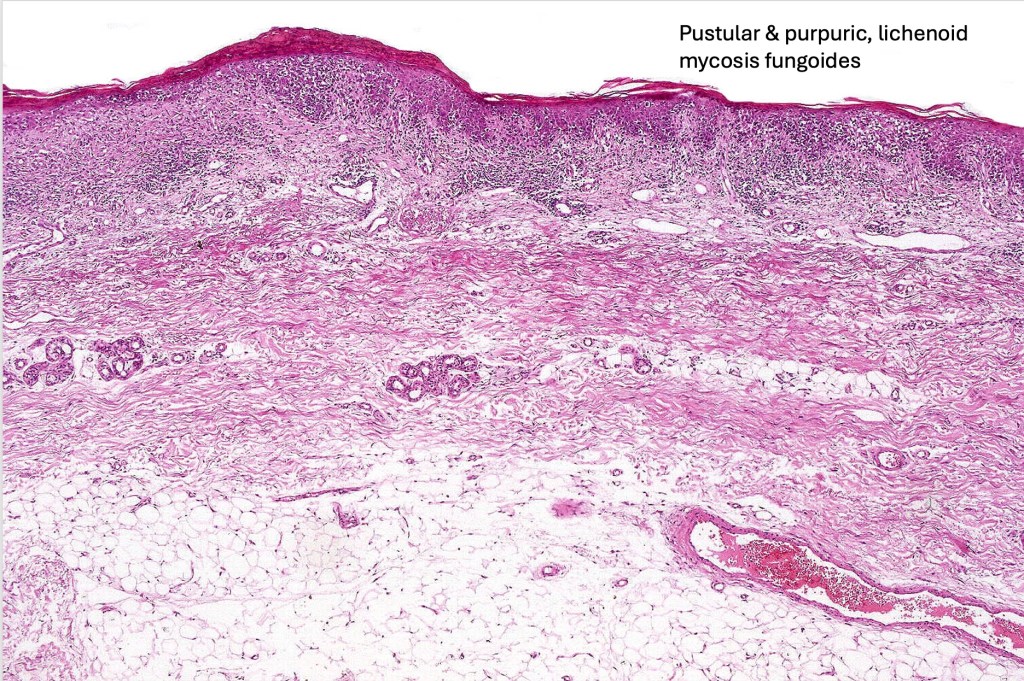

•Rare clinical variants include bullous, hypopigmented, pustular, papular, granulomatous, palmoplantar psoriasiform , acanthosis nigricans-like mycosis, hypopigmented, hyperpigmented, vesiculobullous, pustular, pigmented purpura-like, unilesional, verrucous & invisible (severe pruritus with no visible skin lesions). One patient that I encountered could regularly predict devlopment of a new lesion long before it was clinically apparent just on the basis of a “new itch”.

Histological features

The histological hallmark of mycosis fungoides is the presence of large atypical lymphocytes with a convoluted/cerebriform nuclear border (Sézary cells). These may be found at the epidermal-dermal jnuction and as collections within the epidermis (Pautrier microabscess). These are most easily found in plaque stage disease. The epidermal component can be subtle in patch stage disease and is often lost in tumor stage dsease. The classification into patch, plaque & tumor stage disease is less helpful histologically as the features merge from one to the other. It is all a matter of degree.

Plaque Stage Disease

•Compact hyperkeratosis & patchy parakeratosis

•Acanthosis

•Psoriasiform hyperplasia common

•Epidermotropism is often marked with conspicuous Pautrier microabscesses

•Lichenoid variant & poikiloderma atrophicans vasculare

•Superficial band-like dermal infiltrate of atypical lymphocytes, eosinophils, plasma cells & histiocytes